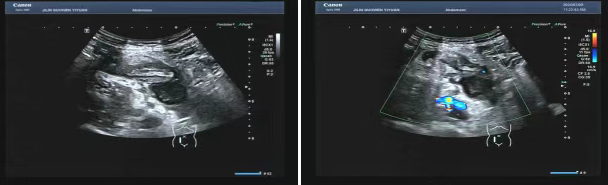

80 歲的張爺爺(化名)因前列腺增生前往國文醫(yī)院就診,泌尿外科為其開具了泌尿系超聲檢查。超聲科醫(yī)生在檢查過程中,憑借敏銳的觀察力,發(fā)現(xiàn)患者右下腹有異?;旌匣芈暟鼔K。醫(yī)生沒有放過這一異常,立即展開進(jìn)一步探查,結(jié)果顯示包塊內(nèi)疑似有闌尾結(jié)構(gòu),且周圍組織存在粘連,還伴有液性暗區(qū)。考慮到老年患者病情往往較為隱匿,癥狀也不典型,醫(yī)生第一時(shí)間與臨床醫(yī)生溝通,建議進(jìn)行緊急處理。隨后,經(jīng)過臨床醫(yī)生詳細(xì)檢查,患者迅速辦理住院并接受手術(shù),術(shù)后病理檢查結(jié)果確診為 “闌尾壞疽伴穿孔合并膿腫形成”。

主治醫(yī)生介紹,老年人患闌尾炎時(shí),癥狀常常不典型,很容易被誤診為腸胃炎或其他疾病。張爺爺僅表現(xiàn)出輕微腹脹的癥狀。倘若不是超聲檢查時(shí)意外發(fā)現(xiàn),極有可能延誤治療,進(jìn)而引發(fā)感染性休克,甚至危及生命。超聲檢查在這類急腹癥的篩查中,發(fā)揮了至關(guān)重要的作用。

“雖然在泌尿系檢查中發(fā)現(xiàn)闌尾病變屬于意外,但這也得益于我院超聲檢查要求的標(biāo)準(zhǔn)切面掃查,以及絕不放過任何異常的職業(yè)習(xí)慣,才能夠捕捉到這一隱藏的隱患。” 超聲科主任表示。國文醫(yī)院超聲科始終秉持 “全面掃查、精準(zhǔn)診斷” 的理念。近年來,已多次在常規(guī)檢查中發(fā)現(xiàn)早期腫瘤、血管栓塞等意外病變,為眾多患者贏得了寶貴的治療先機(jī)。